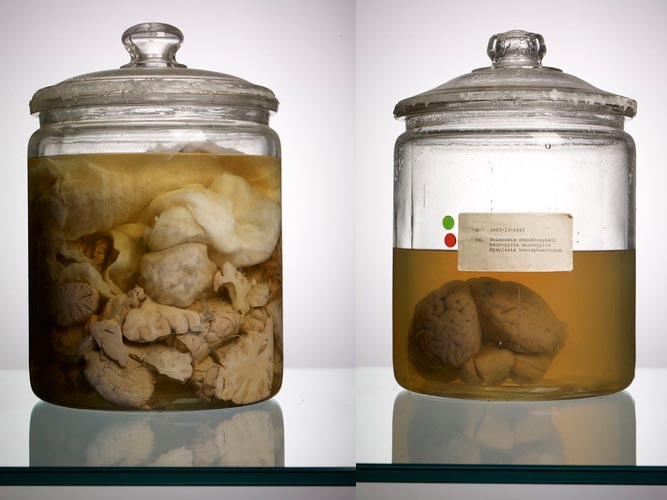

Photographer Adam Voorhes out of Austin, Texas, has documented a collection of approximately 90 human brains that the University of Texas had amassed over the past 30 years.

“Some of them are huge, some of them are really tiny. There was one that had no wrinkles at all,” he told Co.Exist's Stan Alcorn “I don’t even know how to explain it.” He became interested in documenting the collection and after agreeing on the details, Voorhes spent a weekend setting up a studio in the brain lab and created 230 photographs over a two day weekend.

The collection of human brains has been growing for over 30 years by a medical pathologist from the Austin State Hospital, who after routine autopsies, preserved the brains for the collection. Apparently in the mid 1980's the collection was highly sought out and battled over which institution should house and study the brains.